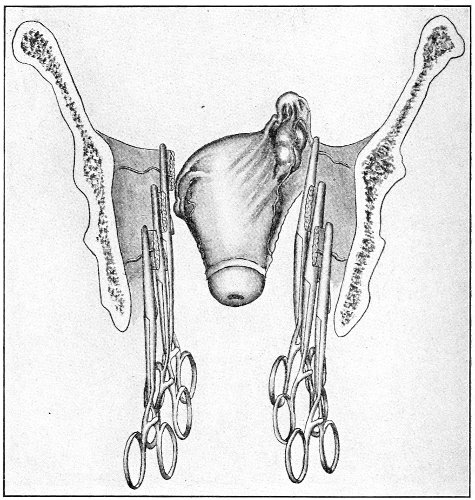

An accurate knowledge of the anatomy and mechanism of the female perineum is essential to an understanding of the nature and treatment of injuries to this structure. The anatomical structures lying between the anus behind and the symphysis pubis in front are those that most directly interest the gynecologist. Proceeding from 57 below upward, we find the following structures lying in superimposed planes: the skin, the superficial fascia, the deep layer of the superficial fascia, the transversus perinæi and the sphincter vaginæ muscles, the anterior layer of the triangular ligament, the posterior layer of the triangular ligament, the levator ani muscle (Fig. 19).

The injuries to the perineum that may result from childbirth are classified according to the position or the direction and extent of the laceration. They are as follows: slight median tear; median tear involving the sphincter ani; tear in one or both of the vaginal sulci; subcutaneous laceration of the muscles and fascia.

All these injuries demand operative treatment. The operation for the repair of injuries to the perineum is called perineorrhaphy. It is called immediate or primary, intermediate, and secondary perineorrhaphy, according to the time after the receipt of the injury at which the operation is performed. The primary operation is done during the first twenty-four hours. The primary operation should always be performed. A careful inspection of the perineum and the posterior vaginal wall should always be made after labor, and any laceration should be repaired within twenty-four hours. The advantages of the primary operation are many. The parts are usually so numb that it is not necessary to administer an anesthetic. No denudation is necessary, and therefore no tissue need be sacrificed. The woman is spared the pain and discomfort of granulation and cicatrization.

The bad results that follow neglect of the primary operation are very numerous, and will be studied hereafter. The injured muscles retract, and, being functionally useless, undergo atrophy, and when finally repaired never possess their former strength. Involution in the vagina and the uterus may be arrested, and all the disasters incident to subinvolution may appear. Vaginal and uterine prolapse occur; the natural supports of the 63 vagina and uterus become stretched, and, though afterward the perineum may be restored, yet it may be found impossible to retain the uterus in its proper position. It is always good surgery to repair an injury as soon as possible.

When practicable, a certain amount of preparation of the patient should be made before the operation of perineorrhaphy. This is most easily effected before the intermediate and secondary operations. The vagina and the vulva should be sterilized, and the intestinal tract should be emptied. Thorough evacuation of the bowels is most important when the sphincter ani has been injured, because it is desirable, after operation for this lesion, that the bowels should not be moved for five or six days. A saline purgative should be administered on an empty stomach about five hours before the operation, and a rectal injection of soap and water should be administered about one hour before the operation. Whatever purgative be employed, it should be administered at such a time that its action shall have ceased by the time of the operation. If this precaution is not observed, there may be a discharge of feces that will infect the wound and interfere with the manipulations.

For operation upon the perineum the woman should be placed in the dorso-sacral position (Fig. 1, page 23).

The special forms of operation will be discussed in the consideration of the varieties of perineal injury.

Slight Median laceration of the Perineum.—In this injury the tear takes place through the fourchette. Posteriorly it may extend as far as the sphincter ani muscle. Upward it may extend for an inch up the posterior vaginal wall. The appearance of this tear is shown in Fig. 33. It will be noted that, as this tear takes place in the median line, none of the muscles that support the perineum are involved, nor are the planes of fascia injured. The perineum is slightly split, and the insertions and origins of the muscles and the fascia are slightly separated. The supporting structures of the perineum and the pelvic floor are, however, uninjured.

Fig. 33.—Recent slight median laceration of the perineum: sutures introduced.

If this tear is detected after labor, it should be closed by the immediate operation. A slight tear involving chiefly the cutaneous aspect of the perineum should be closed by three or four sutures introduced from the outside, as in Fig. 33. The needle should be introduced about a quarter of an inch from the edge of the wound. It should not be passed parallel with the plane of the lacerated surface, but should be swept outward and then inward toward the 68 angle at the bottom of the tear (Fig. 34). It may either emerge at the angle and be re-introduced, or it may be passed directly through to the skin-margin on the opposite side of the wound. If the suture is passed in this way, there will be perfect apposition throughout the whole surface of laceration. If the sutures are improperly passed, there may result only apposition of the skin-edges.

Fig. 34.—Diagram representing the correct and the incorrect method of passing the suture for closure of slight perineal laceration.

If the laceration extends up the posterior vaginal wall, two sets of sutures must be introduced—one on the vaginal aspect of the tear, and one on the skin aspect (Fig. 35).